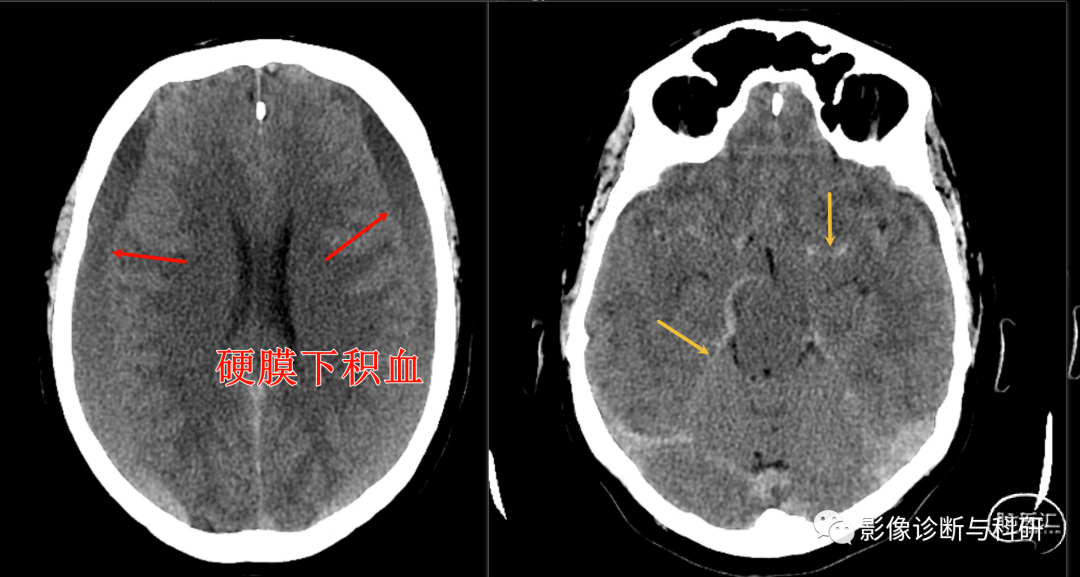

双侧亚急性硬膜下出血伴假性蛛网膜下腔征。